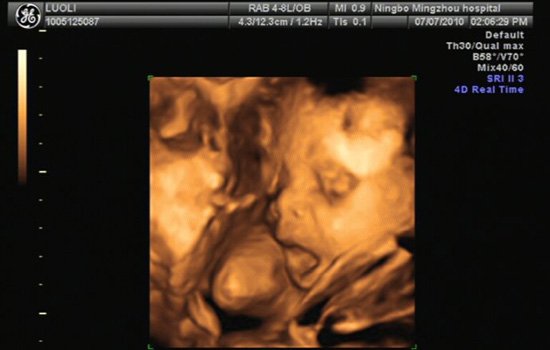

四维彩超

四维彩色超声诊断仪是目前世界上最先进的彩色超声设备。由于四维彩超能够表面成像,胎儿的唇腭裂、四肢发育畸形、脑膜膨出、脊柱裂、腹壁裂等先天畸形能更清晰地查出来。因为四维b超是在三维彩超图像的基础上加上时间维度参数,所以可以观察胎儿实时动态的活动图像。

价格:四维彩超是最先进的,所以价格也是最贵的,至少460元以上,比普通b超、彩色b超、三维b超等贵很多。因为目前在妇产科医学临床上应用还比较少,所以较少人会选择做四维彩超。